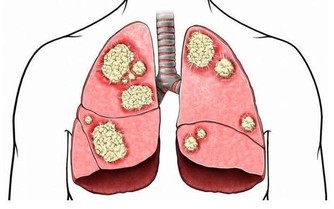

症狀四、全身症狀

膀胱癌的發生也會給患者帶來全身的症狀,比如噁心、食慾不振、發熱、貧血等,這些症狀也是膀胱癌的一些常見症狀,男性朋友們對於這些症狀一定要引起重視,發現了就要及時檢查,以免錯過治療的最佳時間。(參考網站:久久健康網)